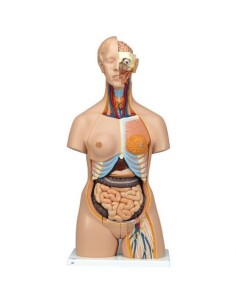

Scopri il Mondo dell’Anatomia con Modelli anatomici di Precisione

Benvenuto su Tuttoanatomia.it, il portale di riferimento in Italia per l’acquisto di modelli anatomici, poster, lettini portatili, simulatori medici e letteratura specialistica. Con i nostri modelli anatomici di 3B Scientific ed Erler Zimmer, leader mondiali nel settore, offriamo un’esperienza di apprendimento senza pari.

Modelli Anatomici Dettagliati per Ogni Necessità

Dal cranio in 22 parti con incastri magnetici ai modelli di colonna vertebrale, da quelli di articolazioni a quelli di cuore, ogni pezzo della nostra collezione è progettato per un’immersione totale nello studio dell’anatomia umana. I nostri modelli, realizzati tramite scansioni di ossa vere, garantiscono un’esperienza tattile autentica e una fedeltà di peso quasi identica agli originali.

Strumenti Didattici Innovativi per l’Educazione e la Pratica Medica

Essenziali per studenti e professionisti, i nostri modelli anatomici sono strumenti didattici che permettono di osservare le strutture anatomiche con precisione, eliminando la necessità di dissezioni o studi invasivi. Sono inoltre utili per spiegare ai pazienti le patologie, rendendo la comunicazione più efficace e risparmiando tempo prezioso.